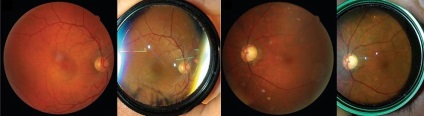

Fig. 3 (fundus).

În general, imaginea cu lentila fundus foarte clar și ostentativ. Deoarece nici unul dintre lampa cu fantă nu este proiectat pentru o astfel de revizuire a fundului de ochi filmare, aceste lentile sunt indispensabile pentru înregistrarea modelului observat.

Fig. 4 (un sondaj pacient).

Datorită câmpului vizual mare utilizarea lentilelor fundus FL1-FL3 cel mai informativ în cazul în care există o vastă în domeniu și vystoyaniya modificări patologice, cum ar fi dezlipire de retină, tumori, retinopatie diabetică, tromboza vaselor retiniene, distrofie periferice, etc.